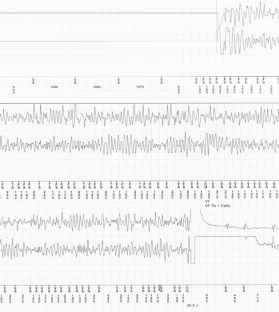

Abb. 1

Abb. 2

Abb. 3

Abb. 4